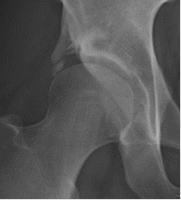

変形性股関節症は軟骨がすり減る疾患で、歩行や立ち上がりに痛みを感じます。レントゲンですり減りの程度がわかりますが、レントゲンで変形が強くても自覚症状が乏しいことがあります。鎮痛剤やリハビリなどの保存療法を行いますが、鎮痛剤がなくては生活できない方、痛みが強く日常生活に支障をきたしている方、レントゲンで変形が著しい方は手術をお勧めします。手術は軟骨損傷の程度によって関節鏡手術、骨切手術、人工関節置換術があります。

臼蓋形成不全やそれに伴う軽度の変形のために、長時間歩行で脚がだる痛くなるなどの症状を訴える患者さんに対しては、リハビリなどの保存療法で改善しない場合に、臼蓋形成術および寛骨臼回転骨切術という2種類の手術療法で対応しております。いずれの手術を行うかは、年齢、股関節の変形の程度、社会的状況を考慮して決めさせていただいております。いずれの手術でも術後1週間程度で車椅子移乗が可能となり、1ヶ月から2ヶ月程度で退院が可能となります。

24歳、臼蓋形成術後2年

43歳、寛骨臼回転骨切術後2年